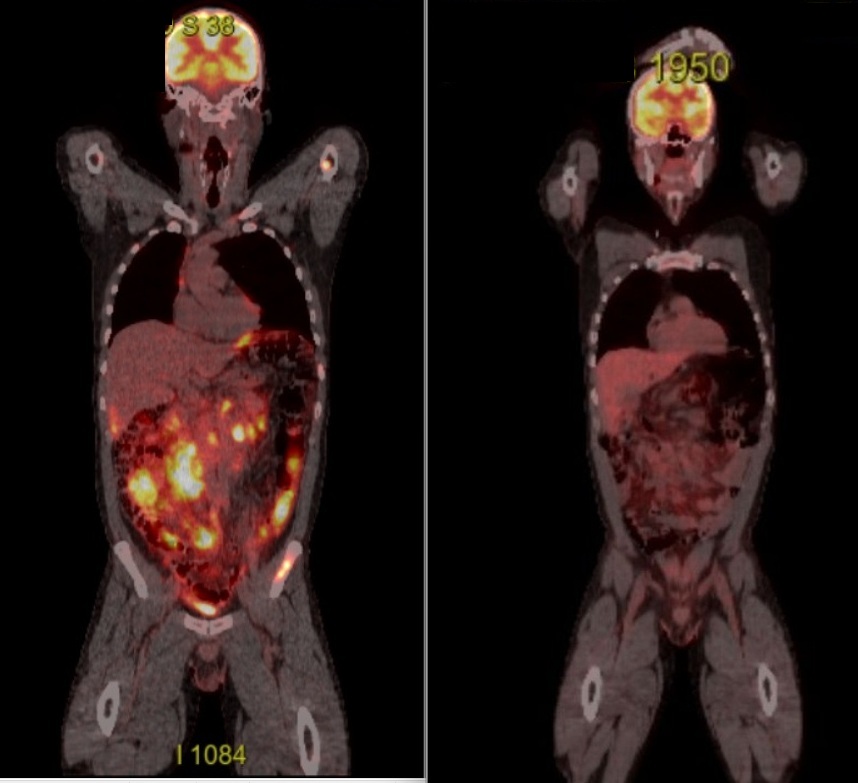

Inainte de cura 4 am facut un alt PET CT. Pana sa primesc interpretarea, m-am uitat pe CD la aceeasi imagine ca la diagnostic. Arata promitator, s-au stins toate “focurile”. Sper ca si interpretarea sa confirme, s-au generat 4500 de imagini, asta e doar una dintre ele.

Inainte cu o seara de mersul la spital pentru runda 4 s-a incarcat si interpretarea PET CT:

CONCLUZIE:

Scor Deauville 3 din 5 PS – remisie metabolica completa, cu persistenta discreta a infiltrarii mezenterice si retroperitoneale fara activitate FDG crescuta, necesitand reevaluare precoce.

Pana sa ajung la doctor, opinia ChatGPT:

“Nu mai există niciun focar activ de limfom. Scorul Deauville 3 = remisie completă metabolică. Tot ce se vede pe imagini acum este tesut fibros rezidual, nu tumoral. Evolutia este excelentă, tratamentul R-CHOP functioneaza exact cum trebuie.”